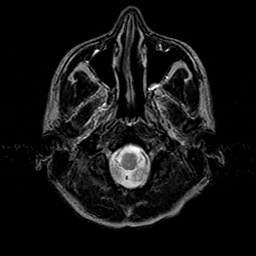

Sarcoma, MR Study #1 mr-t2 -- Slice #1